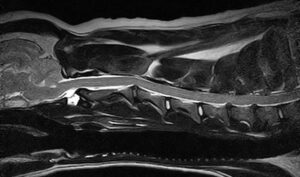

5~6歳以上の去勢手術をしていないオス犬に多い病気ですが、メス犬や去勢した犬に起こることもあります。お尻の筋肉が萎縮した結果、筋肉の隙間から直腸や膀胱が皮膚の下にとびでてしまいます。これにより便が出にくくなったり膀胱炎になったりします。手術をすることで機能回復および今後の致死的な状況を回避することができます。当院では去勢手術→結腸固定→前立腺固定→骨盤隔膜構成筋の縫縮→内閉鎖筋フラップ→浅臀筋フラップの順で通常腹側・臀部左右両側同時に行います。また老化以外に、筋肉が萎縮する原因があったり、腹圧がかかる原因があったりする場合も多いので、再発防止のためそれらの診断・治療も重要です。今回のワンちゃんも無事手術も終わり元気に退院しました。よかったね。